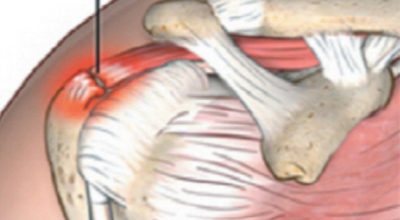

회전근개 증후군은 회전근개에 변형과 파열이 생긴 질환을 말합니다. 회전근개란 어깨와 팔을 연결하는 4개의 근육(극상근, 극하근, 소원근, 겹갑하근) 또는 힘줄로 이루어져 있는 것으로 보입니다. 어깨 근육통을 막연히 오십견으로 알고 방치하다가 치료 시기가 늦어지는 경우가 있답니다. 적절한 시기에 병원에 가는 것이 필요합니다.

그럼 팔과 어깨 활용에 제약을 주는 어깨회전근개파열이 일어나는 원인에 대해 알려드리도록 하겠습니다. 앞서 설명한 것과 같이 골프 같은 어깨 활용량이 많은 운동을 일반적인 때 근력이 약화된 상황에서 급작스럽게 시작하게 된다면 파열 가능성이 높아집니다.

골프 뿐만 아니라 테니스, 수영, 무거운 무게를 드는 헬스 등등 어깨에 무리를 줄 수 있는 운동은 과도하게 하지 않는 것이 좋습니다. 그리고 긴 시간 사무적인 일을 하던가 바르지 않은 자세, 선천적으로 회전근개에 문제가 있다거나 노화로 인한 퇴행성 변화를 겪을 시에는 더욱더 어깨 활용에 주의 해야합니다.